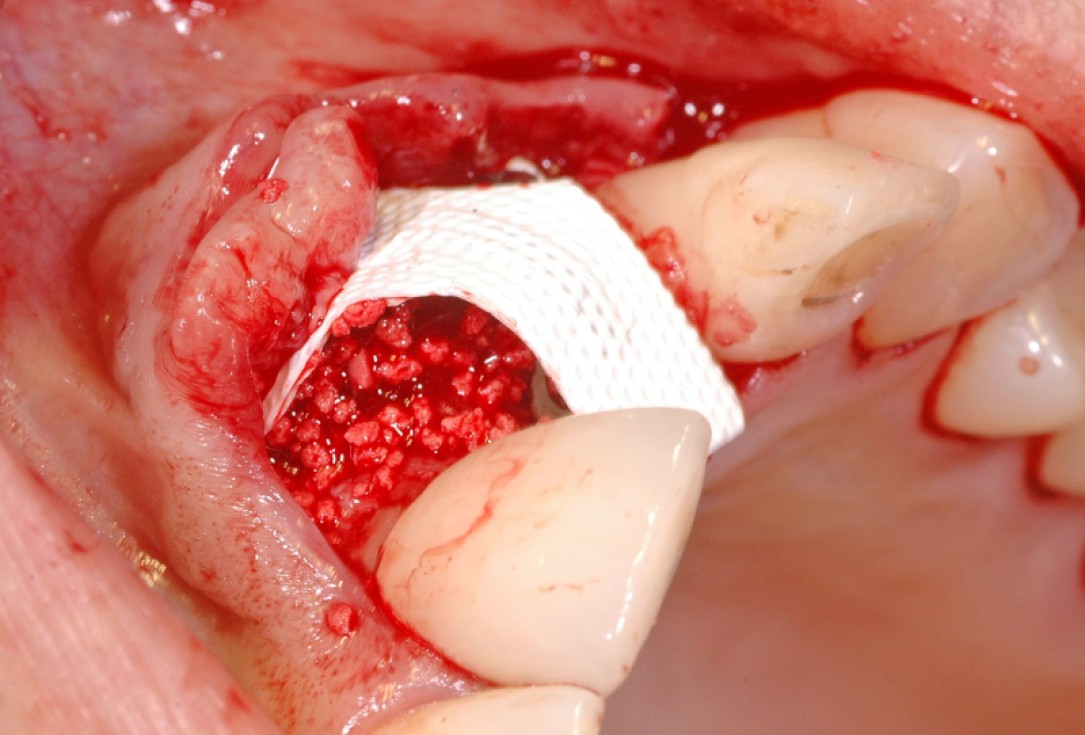

6/18 - Augmentation with maxresorb® and covering with a non-resorbable PTFE membraneGBR together with soft tissue augmentation with mucoderm® and maxresorb® - Dr. S. Scherg